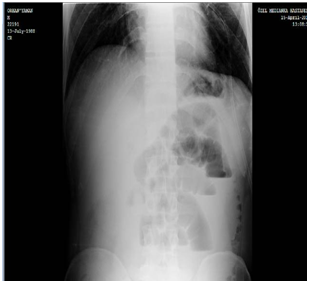

A 28 years-old male presented to the general surgery clinic with a one-week history of intermittent abdominal pain, nausea and distention. He had a history of multiple admissions to different hospitals with similar symptoms during this period. On physical examination, diffuse abdominal tenderness, distension and increased bowel sounds on auscultation were found. Abdominal ultrasound was unremarkable. A plain abdominal X-ray revealed distended small bowel loops and air-fluid levels which indicated ileus. (Figure 1) On laboratory blood tests, WBC was 16.3 x 10(9)/L and C-reactive protein was 119mg/L. Obstructive ileus was considered as a diagnosis and surgical intervention was performed to explore the underlying cause for intestinal obstruction. On exploratory laparotomy, a large ileo-cecal intussusception was found with moderate swelling of the ileum. A right hemicolectomy and an ileo-colic anastomosis were performed.